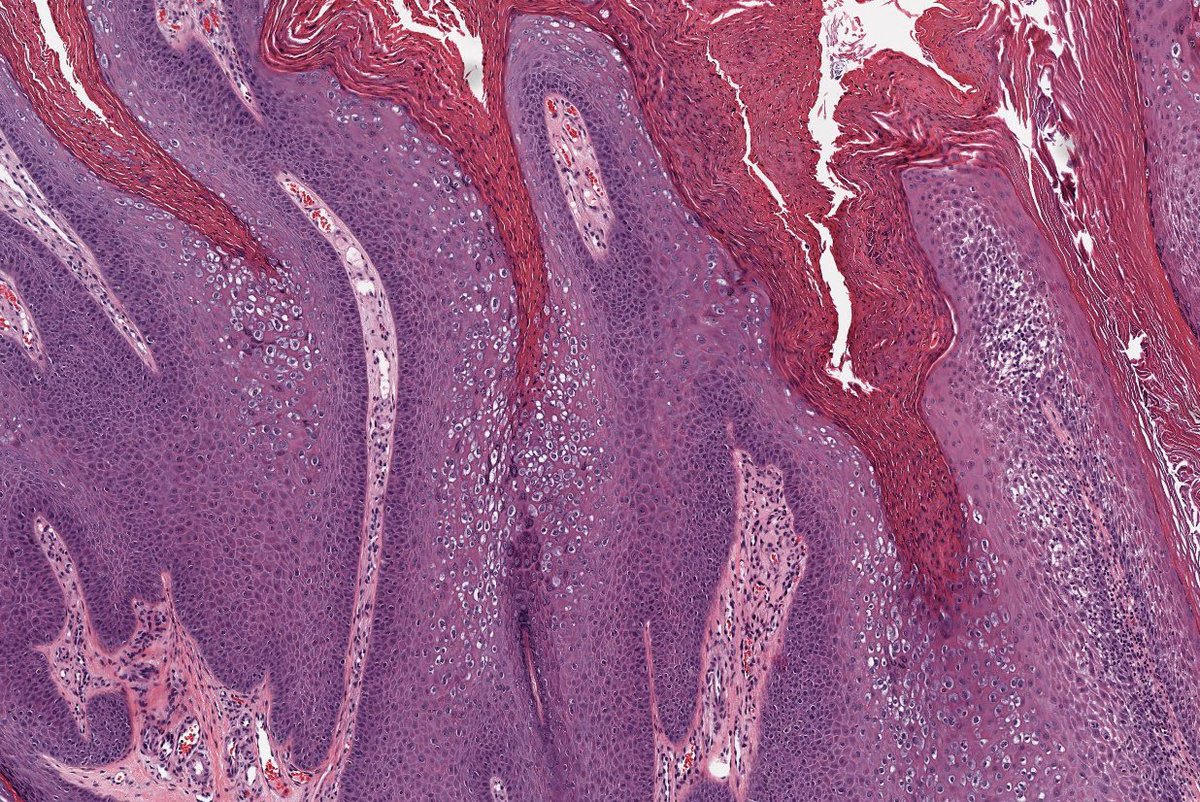

🩸 Talon Noir 📖 Benign ⚾️ 🏀 🏈 ⚽️ Often seen in athletes 🩺 Brown-black macules on foot, most commonly on heel ⚠️ May mimic melanoma 🔬 Acral skin, hyperkeratosis, hemorrhage in stratum corneum +/- telangiectatic vessels in papillary dermis #dermpath #fammed #path4people

Path4People's tweet image. 🩸 Talon Noir

📖 Benign

⚾️ 🏀 🏈 ⚽️ Often seen in athletes

🩺 Brown-black macules on foot, most commonly on heel

⚠️ May mimic melanoma

🔬  Acral skin, hyperkeratosis, hemorrhage in stratum corneum +/- telangiectatic vessels in papillary dermis